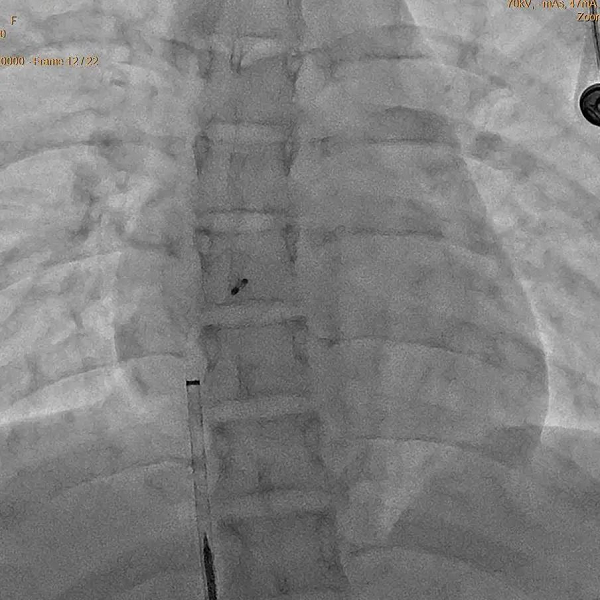

段师傅入院后,在介入组薛亦白副主任的安排下很快就完成了心脏彩超发泡试验检查,证实了高兴才主任的判断。为尽早解决患者痛苦,经积极准备,第二天由心脏外科介入组经验丰富的薛亦白副主任、张伟主治医师等为其实施卵圆孔未闭封堵手术,手术仅用时20分钟便顺利完成。术后第2天段师傅就可以下床活动,偏头疼缓解,术后第4天顺利出院。看着段师傅出院时的背影,连心脏外科的医护人员也都感受到他的那份轻松和愉悦。

手术方法:从大腿根部腹股沟区穿刺股静脉,从人体自身大血管路径(股静脉→髂外静脉→髂总静脉→下腔静脉→右心房→左心房)将封堵器送达并固定于未闭的卵圆孔处,PFO封堵术主体部分耗时约5-10分钟。术后无瘢痕,半年PFO平均闭合率可超过98%。